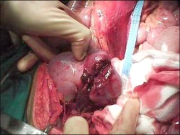

| 09:30, 7 בנובמבר 2012 | פאוכרומוציטומה714.png (קובץ) |  |

225 קילו־בייטים | Motyk | 1 | |

| 09:33, 7 בנובמבר 2012 | פאוכרומוציטומה614.png (קובץ) |  |

185 קילו־בייטים | Motyk | 1 | |

| 09:34, 7 בנובמבר 2012 | תצלוםפאוכרומוציטומה714.png (קובץ) |  |

216 קילו־בייטים | Motyk | 1 | |

| 09:36, 7 בנובמבר 2012 | פאוכרומוציטומה814.png (קובץ) |  |

195 קילו־בייטים | Motyk | 1 | |